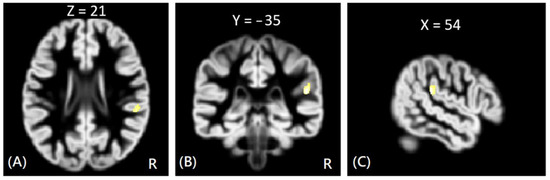

In DTI analysis, the results showed that the offenders (VA + NV + NV) had significantly increased AD, RD, and MD values than those of HC group. The sub-group comparisons further revealed that only the VP group exhibited significantly increased AD, RD, and MD values than the HC group in the right rectus gyrus, as shown in Figure 3. The MNI coordinates of regions with significantly different AD, RD, and MD values between VP and HC groups are listed in Table 3. However, no significant correlation was noted between DTI indices and psychological scores in the significant region.

Figure 3. The voxel-wise DTI analysis of AD values between VP and HC groups. The yellow-white color indicates significantly increased AD values in the VP group in the right rectus gyrus. The images are shown in axial (A), coronal (B), and sagittal views (C).

VP > HC (AD)Rt. Rectus−623−224.15

VP > HC (RD)Rt. Rectus−623−224.38

VP > HC (MD)Rt. Rectus−623−224.30